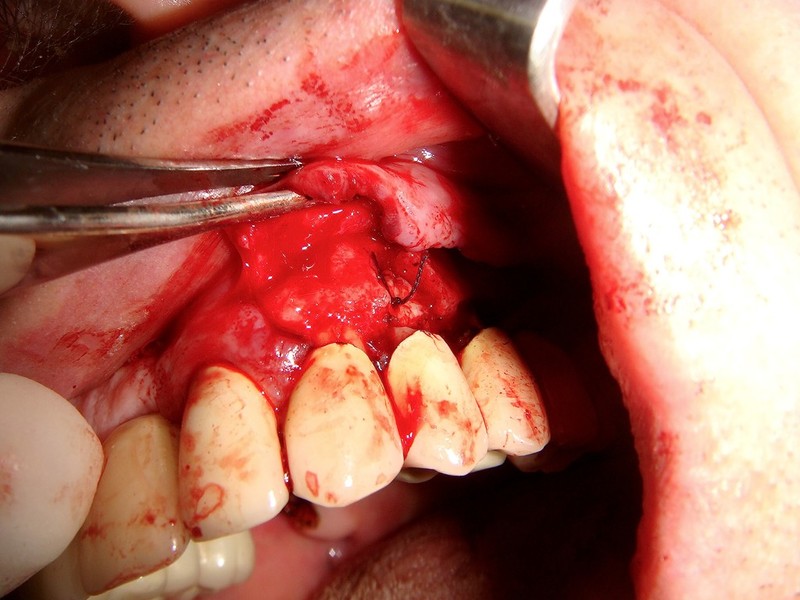

Estrazione di un canino incluso e contestuale inserimenti di impianto e innesto osso eterologo